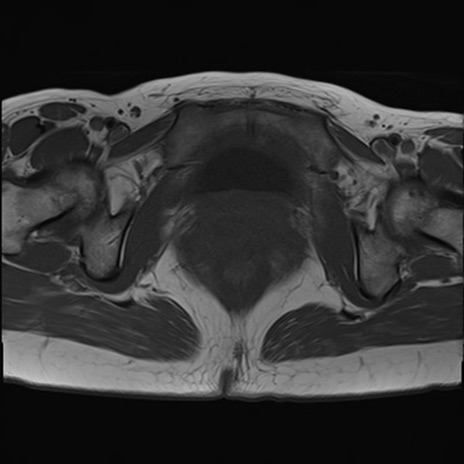

症例39 T1WI(横断像)

MRI(4日後)